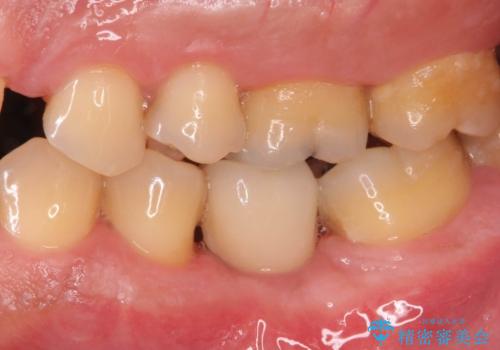

自然な仕上がりと、久しぶりのしっかりと噛める感覚に大変満足いただくことができました。